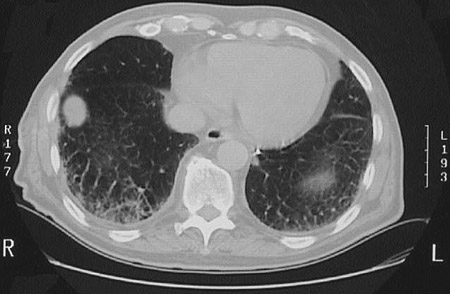

The CT scan of the chest at "lung window" density seen here demonstrates a peripheral right lung mass that proved to be an adenocarcinoma that was removed easily with a wedge resection.